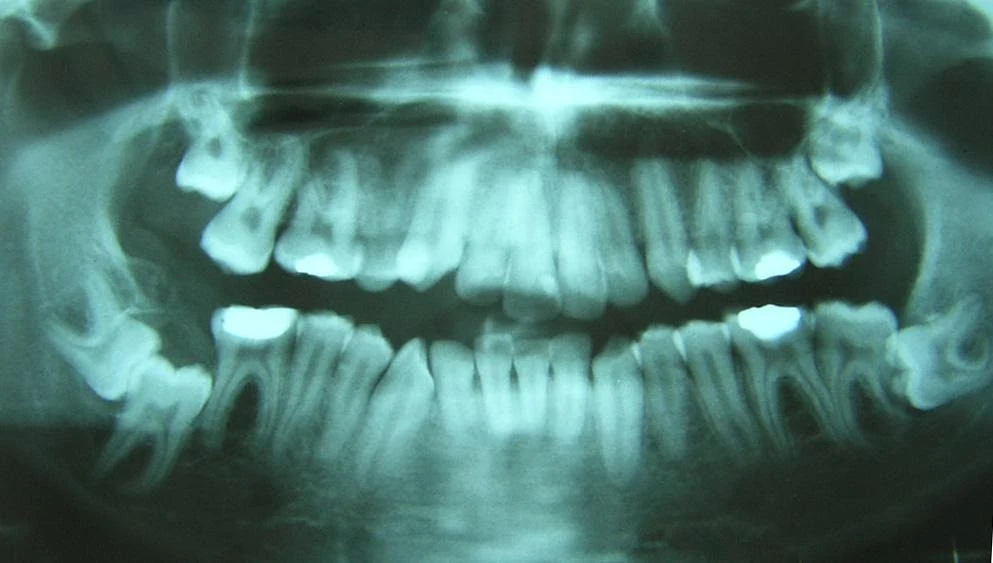

Panoramik röntgen ile çenelerin, tüm dişlerin, çene ve dişlerdeki bir çok rahatsızlığını görebiliriz.Ağızda gözle göremeyeceğimiz çürük, kist ve tümör gibi oluşumların teşhisinde, panoramik röntgenler hekime büyük kolaylık sağlar.